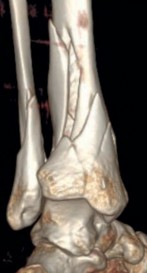

Temporary ankle-spanning external fixation was used to stabilize the fracture and soft tissues. X-rays taken after external fixation showed improved alignment and allowed for better understanding of the fracture pattern (Fig 2.2-2). Computed tomographic (CT) scanning with 3D reconstruction was performed for precise assessment of the fracture pattern of the tibial plafond. The CT revealed displaced fragments with a resultant intraarticular step-off and gap. The distal tibial metaphyseal fracture was multifragmentary. In addition, an associated long oblique fibular fracture was present (Fig 2.2-3).

Fig 2.2-3a–h A CT scan with 3D reconstruction.

a–d Sagittal (a–b), coronal (c), and axial (d) images demonstrate displaced posterior, anterolateral, and medial fracture fragments resulting in intraarticular step and gap. The incongruent tibiotalar joint is best appreciated on the sagittal scan.

e–h The 3D reconstructed images show the external fracture anatomy and general alignment.